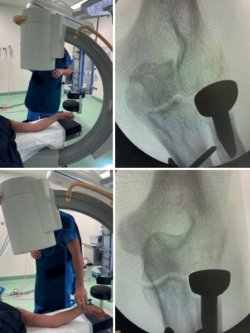

Tanto la rigidez como la inestabilidad pueden estar directamente relacionadas con una elección inadecuada del implante o una mala posición de este(3,4). La literatura anglosajona utiliza el término overstuffing para referirse a la sobrecarga que ejerce la prótesis sobre el capitellum, que puede ocurrir por un exceso de diámetro del implante (se recomienda usar 1 mm menos que la cabeza retirada) o por un exceso de longitud (debe quedar a la altura del margen lateral de la apófisis coronoides, por lo que ha de comprobarse intraoperatoriamente mediante radiología). El término overlengthening es más adecuado para referirse a la mala posición del implante por exceso de longitud(5), consecuencia de una altura de resección insuficiente. Una menor área de contacto entre la prótesis y el capitellum, así como un diferente módulo de elasticidad, justifican la aparición de erosión en el capitellum. La presión entre la cabeza protésica y el capitellum se incrementa notablemente por encima de 2 mm de exceso de longitud(5). Para valorar correctamente la posición de la prótesis, hay que tener en cuenta el déficit de extensión, angulando el rayo de modo que este sea ortogonal al antebrazo y no al húmero distal (Figura 1).

Figura 1. El aparato de rayos ha de situarse perpendicular al antebrazo, para una correcta valoración de la distancia del margen lateral de la apófisis coronoides al borde del implante.